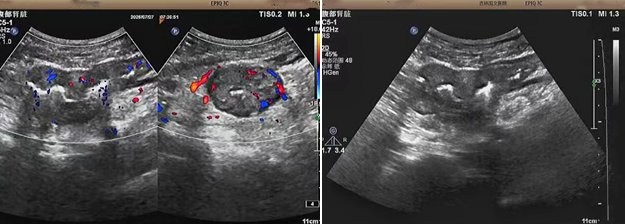

超聲檢查的結(jié)果進(jìn)一步揭示了病情的細(xì)節(jié):下腹部偏左腸壁顯著增厚,原本清晰的層次結(jié)構(gòu)遭到破壞,周?chē)鹃g隙變得模糊,網(wǎng)膜回聲也出現(xiàn)增強(qiáng)的現(xiàn)象;同時(shí),腸腔狹窄的情況也得到了確認(rèn)。經(jīng)過(guò)完善的檢查,最終將病變精準(zhǔn)定位在乙狀結(jié)腸 - 直腸交界區(qū),并且對(duì)病變范圍及周?chē)?rùn)情況做出了評(píng)估,這些關(guān)鍵信息為后續(xù)的診療工作提供了重要依據(jù),讓醫(yī)生們能更有針對(duì)性地制定治療方案。

我院超聲檢查在此次診療過(guò)程中展現(xiàn)出了顯著的技術(shù)亮點(diǎn)。一方面,它能做到 “明察秋毫”,通過(guò)高頻探頭可以清晰地顯示腸壁各層結(jié)構(gòu)的變化,為臨床判斷病變性質(zhì)提供了客觀、準(zhǔn)確的依據(jù),讓醫(yī)生能更清晰地了解腸道內(nèi)部的病變狀態(tài),另一方面,它實(shí)現(xiàn)了 “精準(zhǔn)評(píng)估”,不僅準(zhǔn)確找到了病變的位置,還能全面評(píng)估病變對(duì)周?chē)M織的影響,這對(duì)于協(xié)助醫(yī)生制定科學(xué)合理的治療方案起到了至關(guān)重要的作用,有助于提高治療的有效性和安全性。